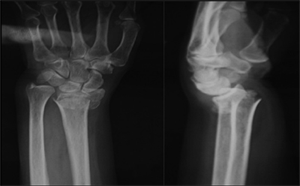

ճաճանչոսկրի դիստալ մետաէպիֆիզի տեղաշարժված կոտրվածք

Կոնտրոլ` համադրումից հետո

Երկրորդային տեղաշարժ 7-10 օր անց